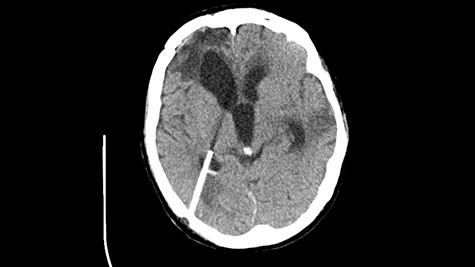

A 49-year-old patient presented after surgical treatment of nasal polyps, with headache and consciousness disorders (behavioral changes, drowsiness and allophenic orientation disorders). Computed tomography (CT) scan showed (Fig. 1) a presence of blood in fluid spaces, widening of the ventricular system (without active hydrocephalus features) and presence of air in the frontal horns of the lateral ventricles and features of cerebral edema. Due to the subarachnoid hemorrhage, an angio-CT and CT scan was performed, showing no vascular malformation. The patient's condition deteriorated with a drop in Glasgow Coma Scale (GCS) to 9, strongly expressed meningeal syndrome and a fever of > 38°C. In the performed cerebrospinal fluid examination a typical picture for bacterial infection, cultures negative. Treatment was implemented in accordance with the neuro-infections algorithm. Clinical and laboratory features of neuroinfections have withdrawn. The neurological condition of the patient improved to GCS 11. Control head CT (Fig. 2) showed enlargement of the ventricular system with cerebrospinal fluid transudation.

Head CT after polypectomy—presence of blood in fluid spaces, widening of the ventricular system, presence of air in the frontal horns of the lateral ventricles, features of cerebral edema. (Department of Neurosurgery Neurotraumatology and Pediatric Surgery own material).

In described case, a head CT scan after polypectomy confirmed the subarachnoid hemorrhage (Fig. 1). In addition, the presence of air in the ventricular system was visible, and presence of defects of the upper left orbital wall and ethmoid on both sides (Fig. 3). In the CT scan sphenoid sinus, frontal and ethmoidal sinuses on both sides and right maxillary sinus airless, filled with blood and soft tissue. The changes also concerned the lateral part of the left maxillary sinus (Fig. 4).